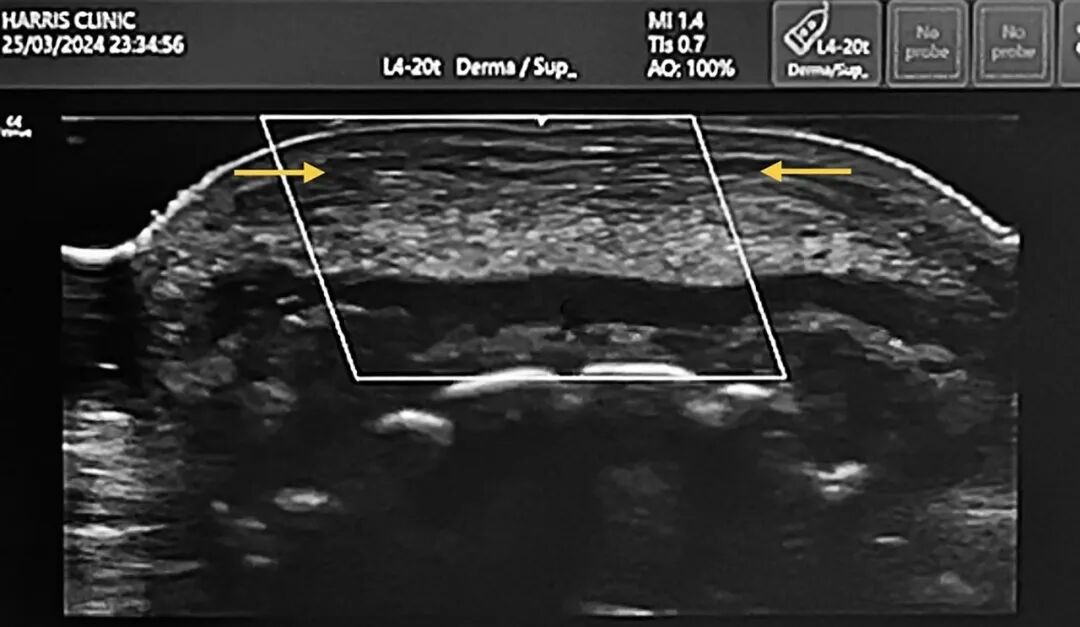

图2. 下唇部位的高频超声图像,示非计划性注入口轮匝肌缘部的透明质酸填充剂(箭头之间),符合陈旧性过度填充的影像学表现。

超声可为上述复杂机制提供重要影像学参考,高频超声成像可清晰显示:填充剂分布呈不均质性,即便非刻意注射,也常出现肌内置入现象;填充剂可沿筋膜或肌肉平面发生间室内弥散;且经透明质酸酶干预后,超声回声信号物质仅部分消减,而非完全消失。上述结果提示,酶解效果存在多样性差异,并非呈现「完全溶解 / 未溶解」的二元对立结局。

然而,超声发现仅为描述性而非确定性的,且回声模式不具备特异性——低回声区域可能代表残留透明质酸、水肿或积液,而纤维化通常呈高回声,可能部分遮挡下方的填充剂。陈旧性填充剂往往会产生混合回声,需要结合临床背景进行解读,且图像的采集与解读高度依赖操作者。设备质量也存在很大差异:与低分辨率的手持超声设备相比,高频医用超声系统(15–22MHz)可提供更优异的轴向分辨率与侧向分辨率;手持设备可能难以区分填充剂与水肿、深部脂肪或肌肉等邻近低回声结构,也可能无法清晰显示细微的纤维化改变。目前,业内尚无针对“完全清除”的统一超声诊断标准,因为即便临床外观已得到改善,残留凝胶、水肿与纤维组织增生仍可能同时存在(图3,视频1、视频2)。